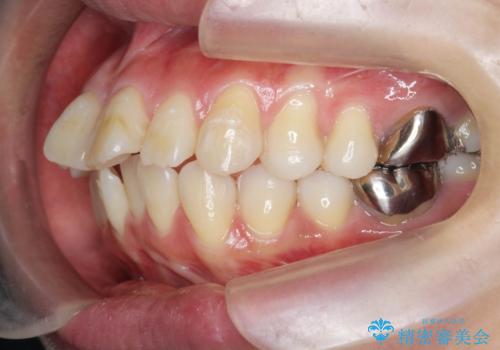

捻れた奥歯 突き出た前歯を治したい

- 出っ歯に見える前歯、捻れてしまった小臼歯の改善を求めて来院されました。

マウスピースでは改善の難しい小臼歯のねじれをまず部分ワイヤー矯正で改善し、その後マウスピース矯正で前歯の突出感を改善します。

時間はかかりましたが、捻れ、かみ合わせ、前歯の角度の改善が達成され満足いただくことができました。